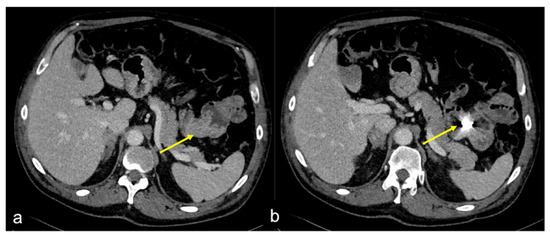

| Dieulafoy Lesion (Figure 27) | Melaena, haematemesis, haematochezia, or a combination of more than one of these signs, depending on the location of the lesion. | Abnormally enlarged submucosal vessel, which may appear tortuous, linear or as a non-specific “blush” of contrast medium at the mucosal/submucosal level. |